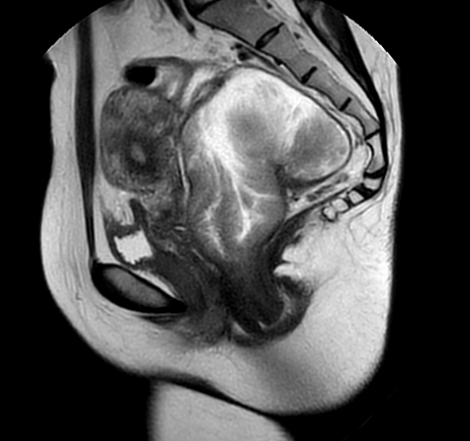

患者术前核磁共振结果

胃结直肠外科副主任医师李成发表示,患者既往已有两次肠镜下直肠腺瘤ESD手术切除史,本次为第3次局部复发,高度怀疑有腺瘤恶变可能。肿瘤距肛缘2~3cm,为超低位直肠肿物,肿物较大,肠镜下ESD手术难度大,且术后出现的并发症几率较高,很难到达根治。

按照既定计划,手术顺利,直肠肿物被完整切除,手术保肛成功。术后病理高分化绒毛状腺癌(I期)。